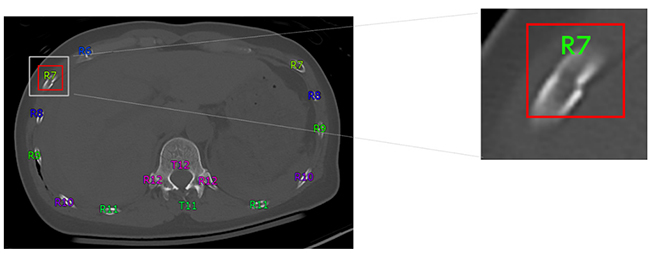

CT画像から三次元解析する同社技術を活用することで,骨表面を構成する皮質骨の断裂が認められる箇所を肋骨骨折の候補として検出する。

骨折箇所の検出イメージ

(1) 骨番号の「自動ラベリング機能」と併用することで,肋骨骨折が生じている骨番号が自動で付与され,所見文を作成する際の負荷を軽減する。

「自動ラベリング機能」と併用した時の検出イメージ